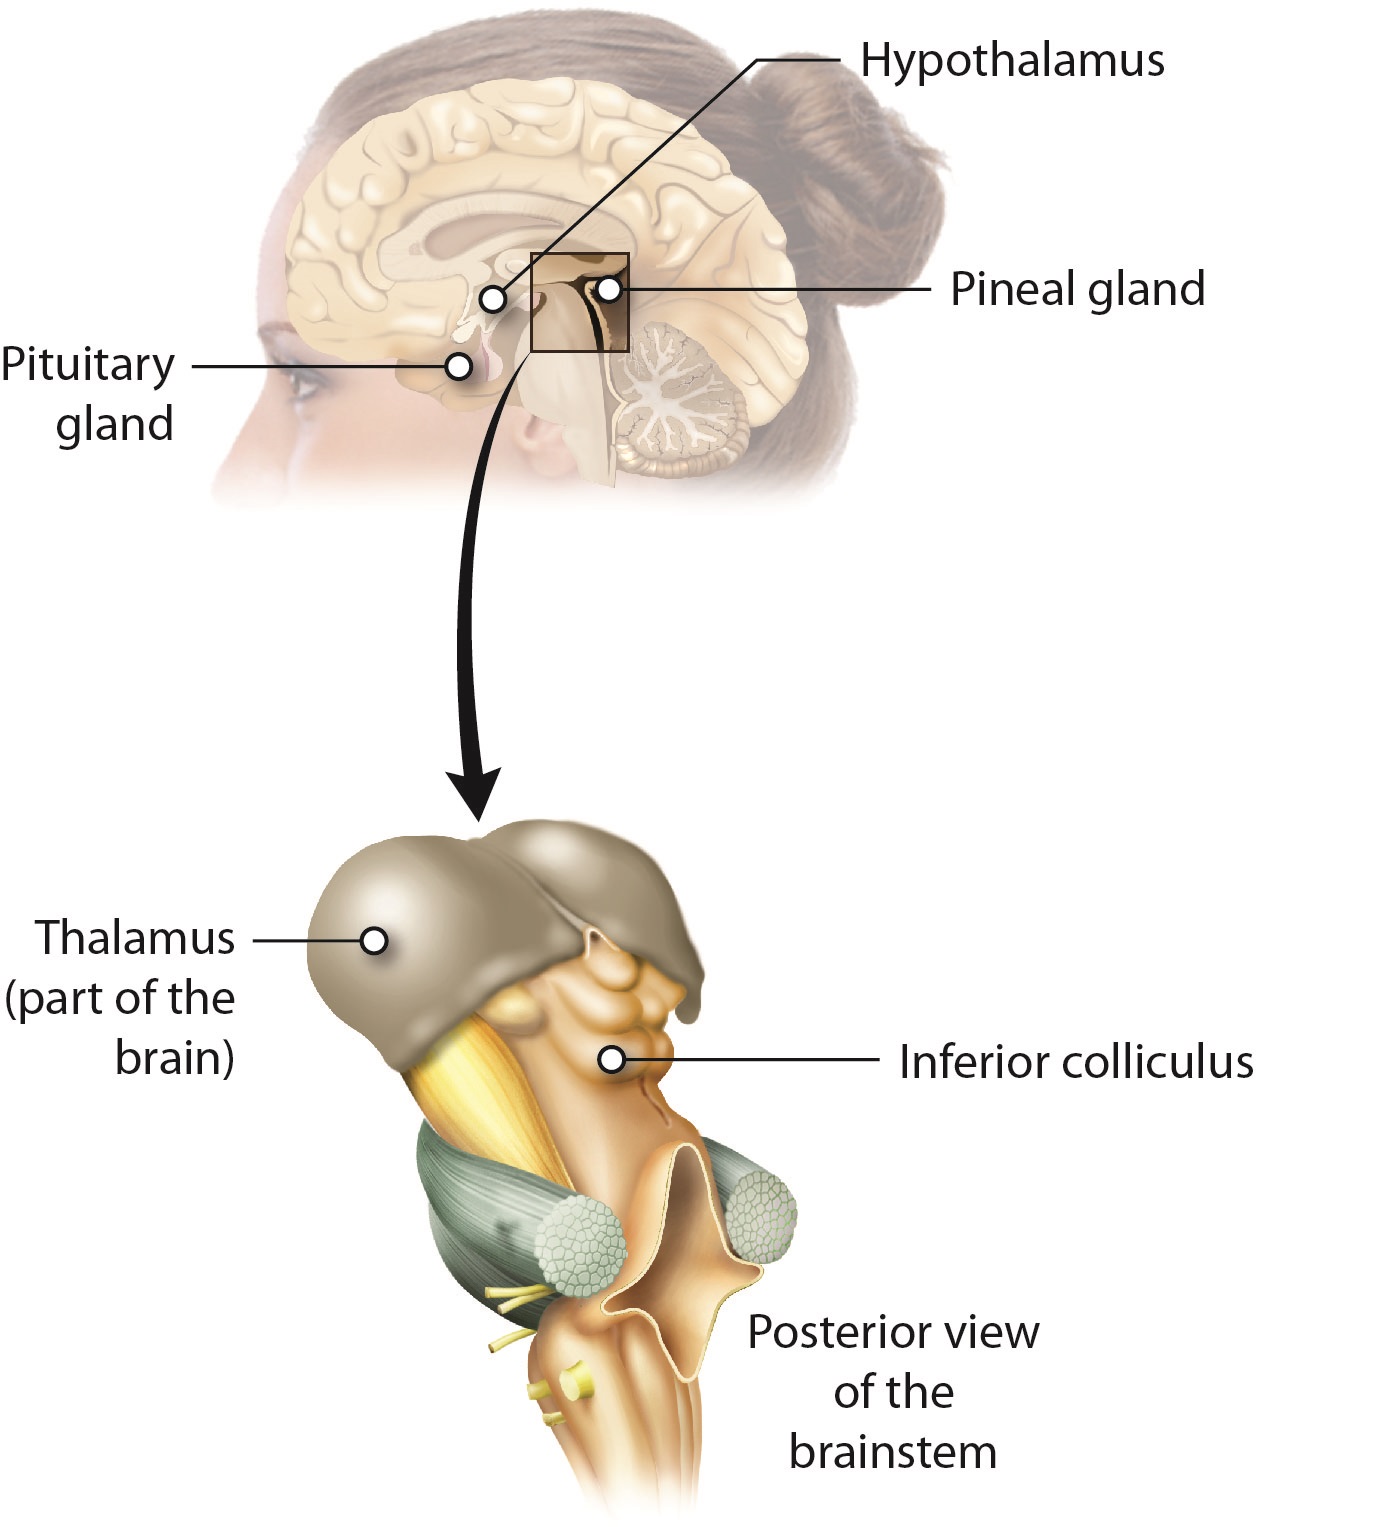

Как работает центр насыщения в гипоталамусе: визуальные иллюстрации